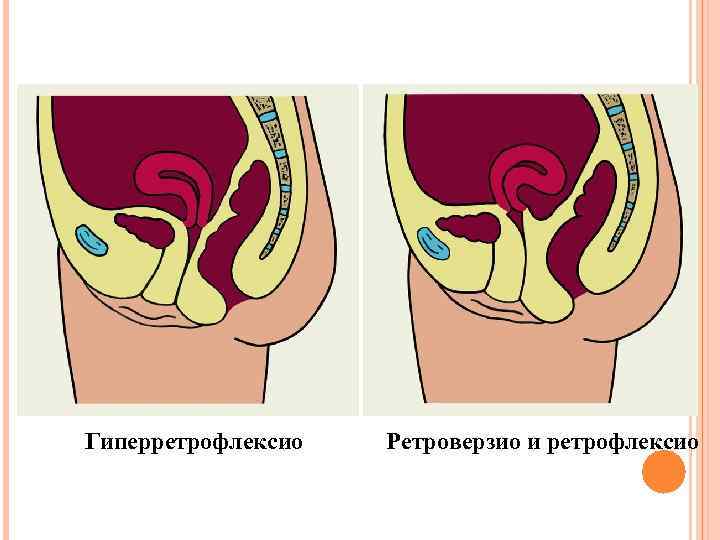

Гиперретрофлексио Ретроверзио и ретрофлексио

Гиперретрофлексио Ретроверзио и ретрофлексио